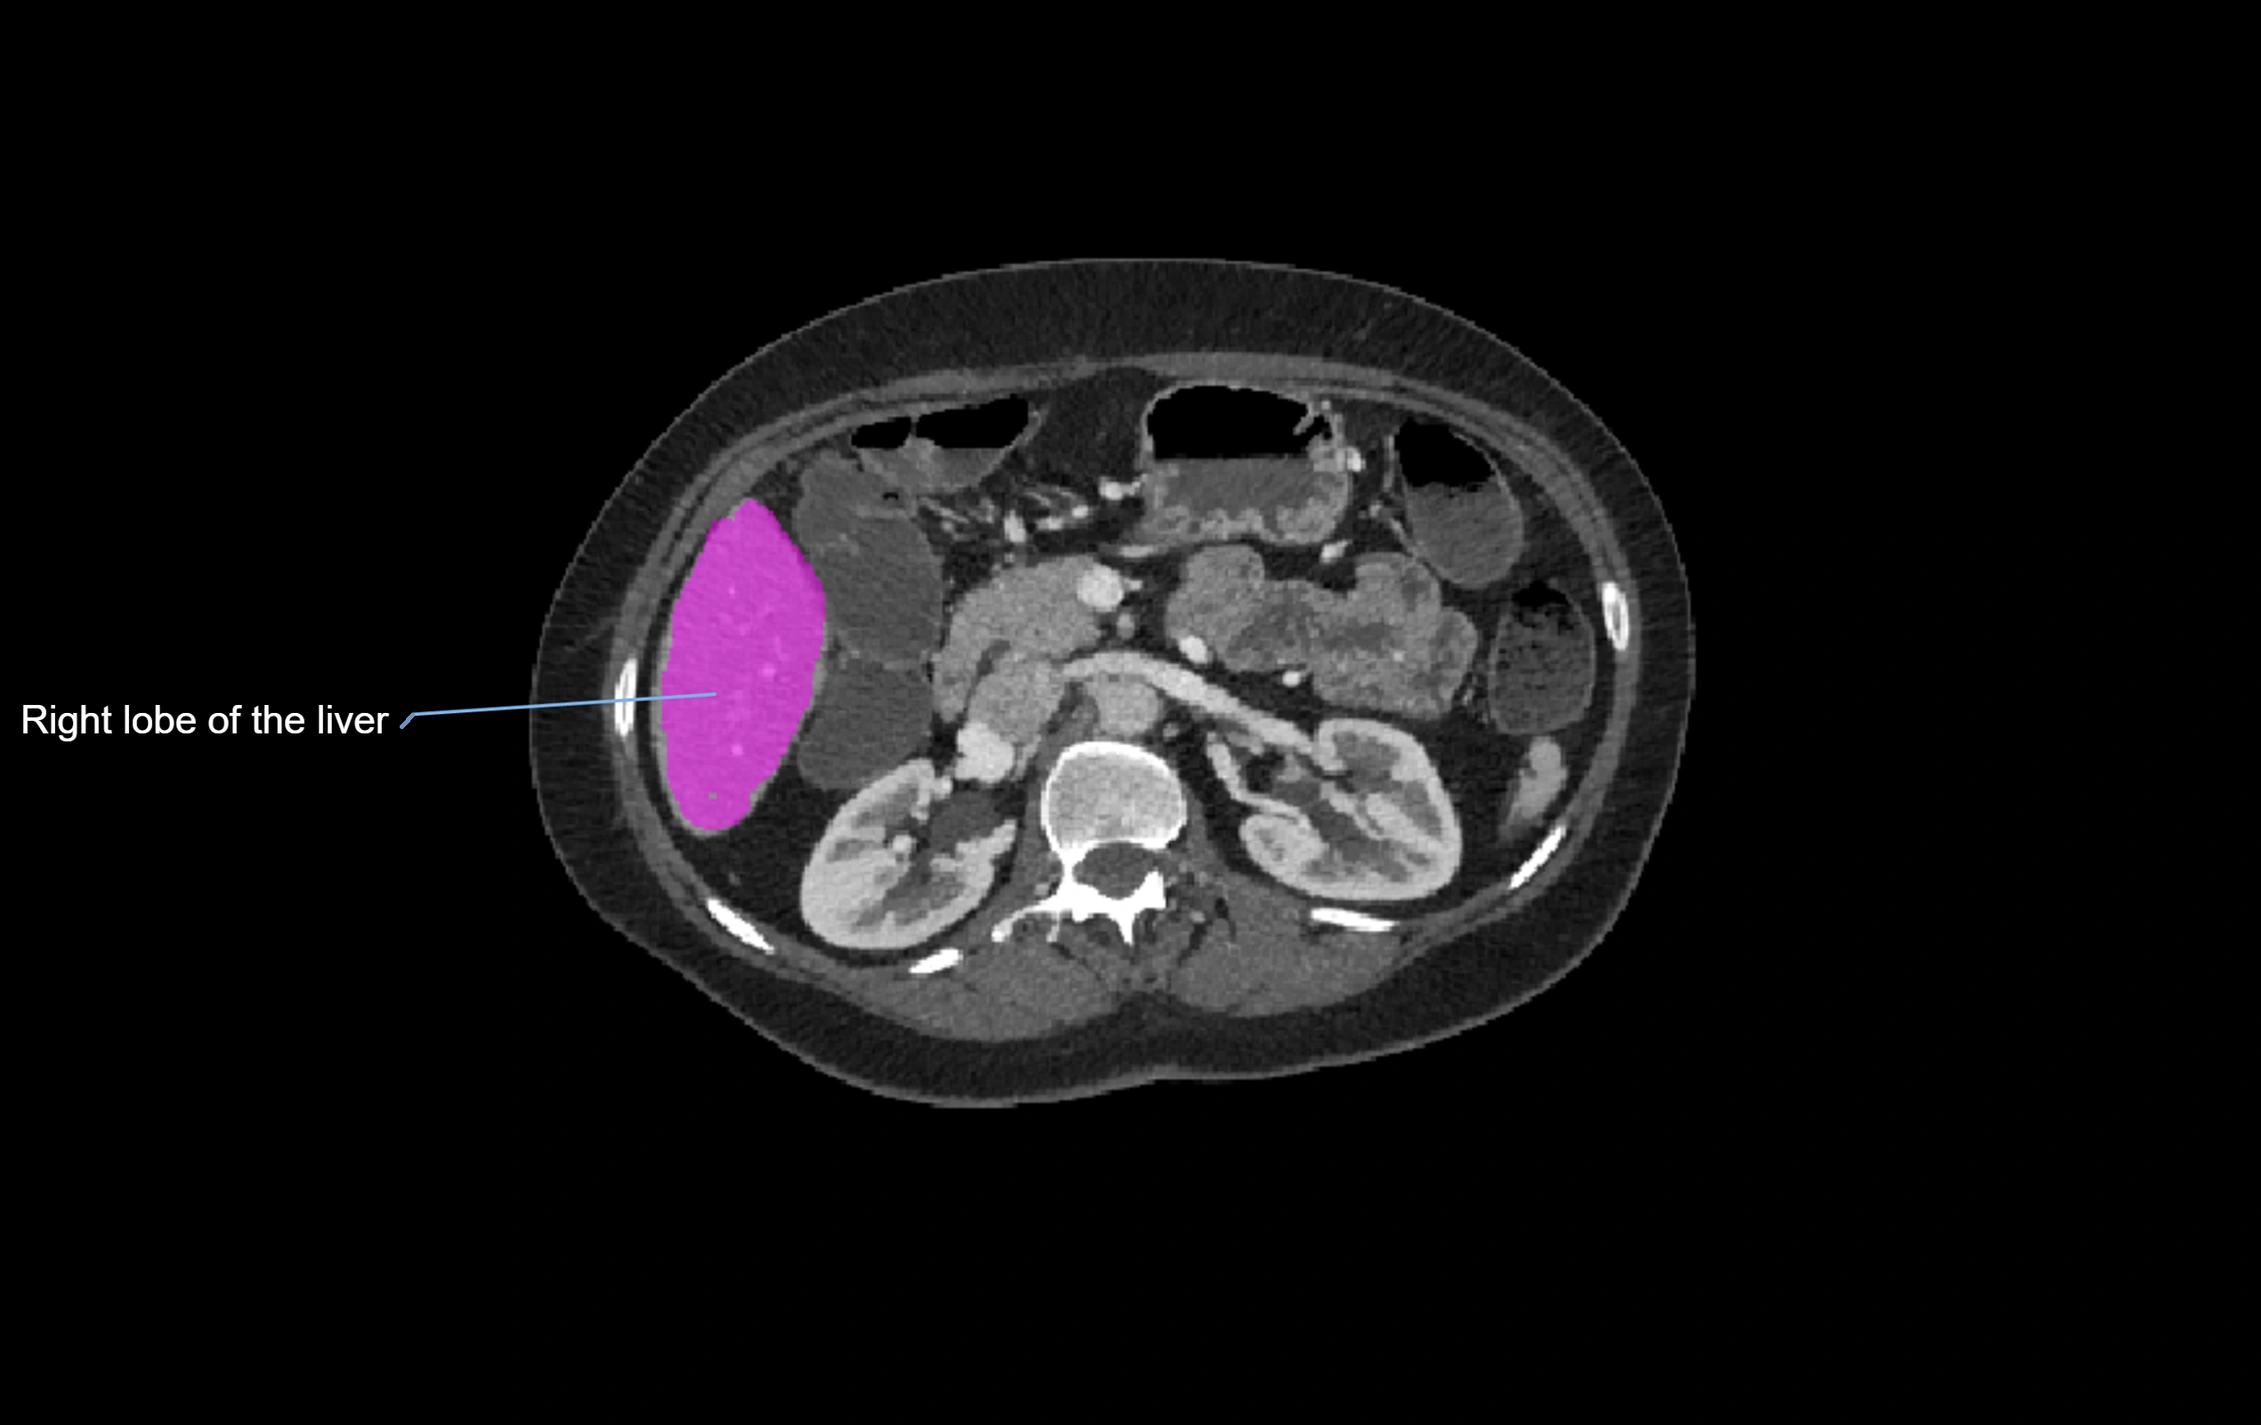

CT Appearance

CT Pre-Contrast:

• Caudate lobe appears as a soft-tissue density, isodense to the rest of the liver

• Enlargement may be appreciated in cirrhosis or Budd–Chiari syndrome

CT Post-Contrast:

• Homogeneous enhancement in the portal venous phase, similar to rest of liver

• Independent venous drainage into the IVC may be visualized

CT Venous Phase (functional significance):

• Caudate lobe often enhances relatively more than other lobes in Budd–Chiari syndrome, due to preserved venous outflow